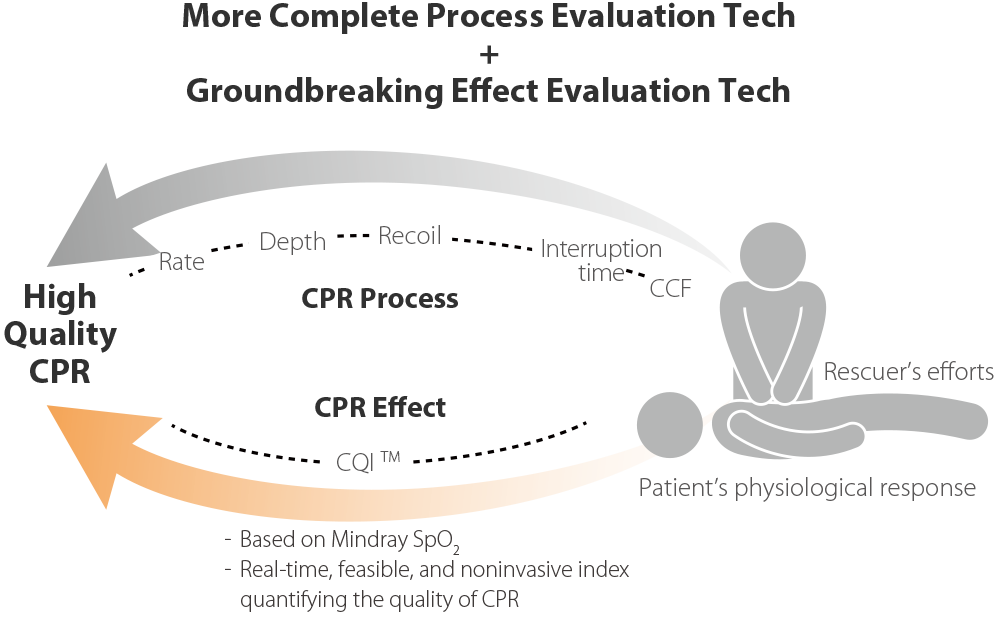

Triangle de sauvetage, plus complet

- Les protocoles de dĂŠbriefing structurĂŠs du D60 amĂŠliorent les performances des ĂŠquipes de rĂŠanimation lors de rĂŠanimations ultĂŠrieures.

RĂŠanimation plus rapide

DĂŠbriefing structurĂŠ

- Les protocoles de dĂŠbriefing structurĂŠs du D60 amĂŠliorent les performances des ĂŠquipes de rĂŠanimation lors de rĂŠanimations ultĂŠrieures.